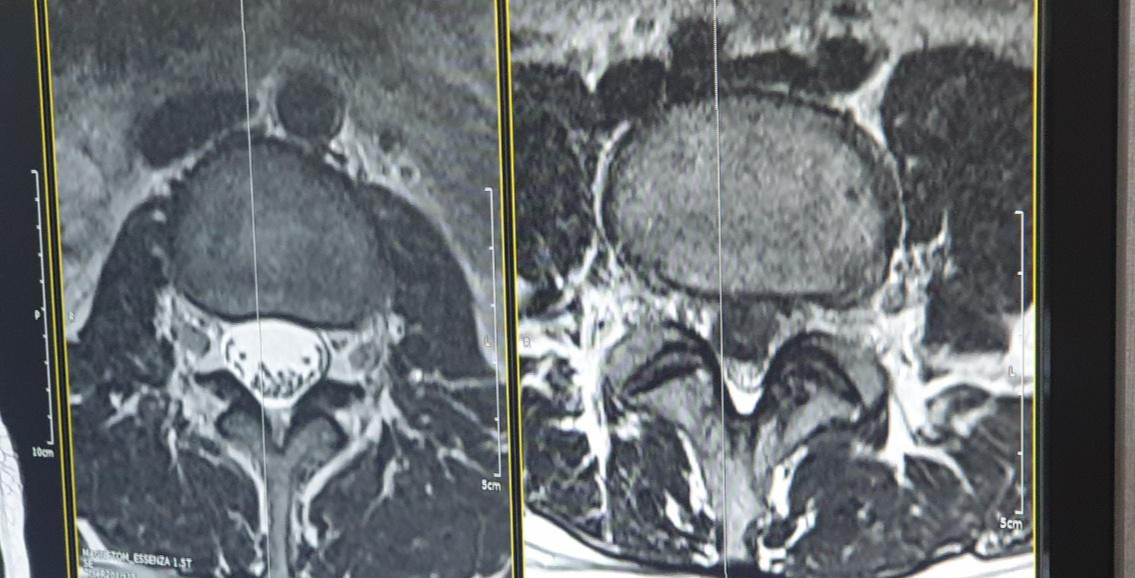

일단 어느정도 였는지 디스크 사진을..

일단.. 근육이 .. 오호.. 까만게 근육인데

엄청나네요! 역시 재무부 장관님.. 근력이 장난이 아닙니다.

가운데 하얀 심지가 신경통로 입니다.

그위에 녹용 절단면처럼 생긴게 디스크죠

우측 사진을 보시면 디스크가 터져서 신경통로는

쨔부쨔부해버려 거진 안보이다 싶이 한게 보이실 겁니다.

네... 엄청나게 터져버렸습니다.